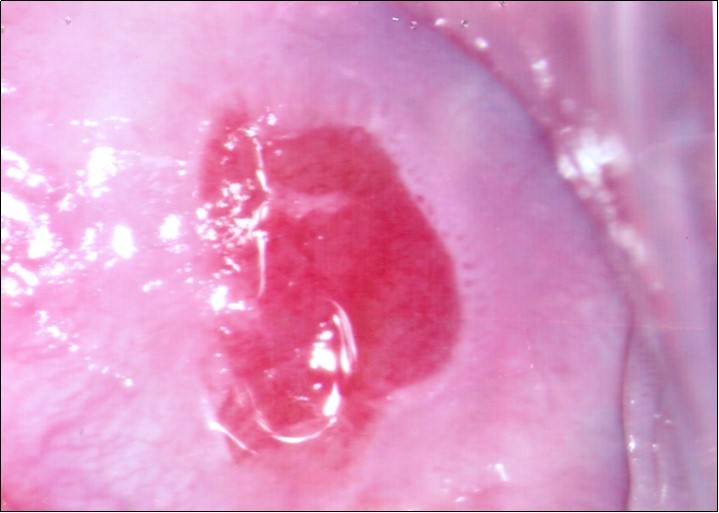

Repeat colposcopy was performed after 6 weeks. This revealed a small ulcerated area at the site of previous biopsy with rolled healing edges, and a separate small ulcer at the 12 o’clock position. (Figure 2a, Figure 2b, Figure 2c) Careful inspection of the buccal mucosa revealed similar ulcers in the left buccal region. (Figure 3)

Figure 2b.Repeat colposcopy (high magnification)